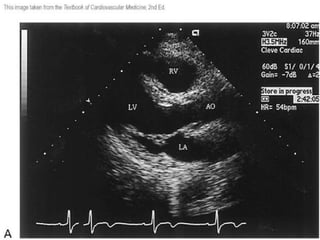

Tractos de Salida

• Desde un punto de vista funcional el TSVI

se extiende desde el borde libre de la valva

anterior de la válvula mitral hasta el anillo

de la válvula aórtica

• El TSVD se extiende cefálicamente y hacia

la izquierda desde la porción anteromedial

del a nillo de la válvula tricuspide hasta el

anillo de la válvula pulmonar

Tractos

de salida

de VI y

VD: